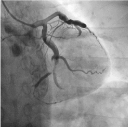

Trans-radial coronary angiogram revealed tortuous and aneurysmal dilatation (ectatic vessels) of all three major coronary arteries (Figure 3a, 3b) with huge thrombus in the proximal segment of left circumflex (LCx) artery, the culprit lesion was identified. Left coronary system was engaged with XB 3.0 6-French guiding catheter through right radial access with 6F sheath. The lesion was crossed by Run through NS floppy (Terumo) hydrophilic 0.014 inches wire. Among different strategies to deal with huge thrombus burden such as Plain Old Balloon Angioplasty (POBA), thrombus aspiration and intracoronary glycoprotein IIb/IIIa inhibitor, we proceeded with thrombus aspiration. Thrombuster II (Kaneka Corporation) thrombus aspiration catheter introduced into the target vessel and suctioning performed. Blood clots aspirated as shown (Figure 4). After few aspirations, failed to do further suctioning and planned to flush as the catheter may get blocked from aspirated thrombus. Some degree of resistance was felt while removing the catheter from the vessel. The thrombus aspiration catheter finally came out with slight pulling force but noted that the tip was missing (Figure 5). Angiographically, the tip of Thrombuster II catheter seen attached to the guidewire (Figure 6). The guidewire can move freely along the mid and distal LCx but failed to withdrawal at the proximal LCx area.

Figure 3a. Left coronary artery Figure 3b. Right coronary artery